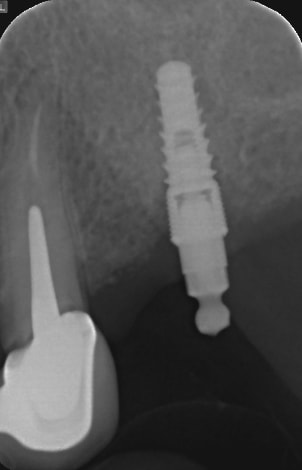

J'ai une patiente qui vient avec comme désiderata la suppression d'une petite PAP secteur 2 qui est maintenue par un attachement boule sur implant.

Elle ne connait pas la marque de cet implant, posé il y a 8 ans, qui est parfois douloureux à cause d'une petite mucosite et d'une legère perte osseuse.

Je lui ai proposé la réalisation d'un bridge sur implant 24-26 avec dépose de cet implant.

En effet, ni la position ni l'angulation ne me convienne.

Je déposerais l’implant (Euroteknika Natura?) sans hésiter avec comblement puis poserais 3 implants pour 4 dents

C'est bien un naturall euroteknika en tout cas